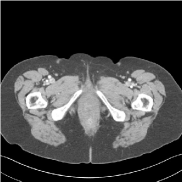

This special case of SUPER corresponds to the case where SUPER excludes the unsupervised regularizer, while only involves the data-fidelity and a supervised regularizer in the MBIR cost, i.e., β=0𝛽0\beta=0 and μ0𝜇0\mu\neq 0. In this case, the proposed SUPER model is similar to a generalized block coordinate descent-based network by replacing a simple denoising autoencoder [28, 29, 30] with a general CNN that forms our supervised regularizer. This SUPER is also similar to the plug-and-play ADMM-Net method except that the inputs to each supervised network are the preceding reconstructions, while plug-and-play ADMM-Net updates inputs to the network (denoiser) based on auxiliary variables in the ADMM algorithm. Here, we used μ=1×106𝜇1superscript106\mu=1\times 10^{6}, which worked well for the plug-and-play ADMM-Net method, for this special case of SUPER. Fig. 7 shows a comparison between plug-and-play ADMM-Net, SUPER without unsupervised regularizers (in both training and testing), and the full SUPER version with ULTRA regularization (β=5×103𝛽5superscript103\beta=5\times 10^{3}, μ=5×105𝜇5superscript105\mu=5\times 10^{5}). All these methods used WavResNet as their denoisers/supervised networks. In this example, SUPER with only a supervised regularizer (SUPER-WRN-β=0𝛽0\beta=0) outperforms the plug-and-play ADMM-Net (ADMM-Net (WRN)) by 1.6 HU RMSE and provides sharper image details. Comparing SUPER-WRN-β=0𝛽0\beta=0 and the full SUPER-WRN-ULTRA scheme, we observe that the latter provides a lower RMSE and higher contrast image features than the former that excludes the unsupervised component. This again shows the effect of the unsupervised ULTRA model (in capturing local image details better with a union of learned transforms) in the SUPER scheme.

Refer to captionADMM-Net (WRN)RMSE = 32.90 HURefer to captionADMM-Net (WRN)RMSE = 32.90 HU

Refer to captionSUPER-WRN-β=0𝛽0\beta=0RMSE = 31.32 HURefer to captionSUPER-WRN-β=0𝛽0\beta=0RMSE = 31.32 HU

Refer to caption SUPER-WRN-ULTRARMSE = 29.74 HURefer to caption SUPER-WRN-ULTRARMSE = 29.74 HU

Refer to caption ReferenceRefer to caption Reference

Figure 7: Reconstructed images of L192 slice 150 with WavResNet plugged ADMM-Net, SUPER-WRN-β=0𝛽0\beta=0 (both training and testing), and SUPER-WRN-ULTRA (β=5×103𝛽5superscript103\beta=5\times 10^{3} in both training and testing), respectively, shown with the reference image.